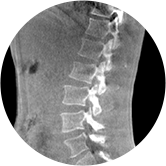

腰椎

精准诊断

手术方案规划

术后随访